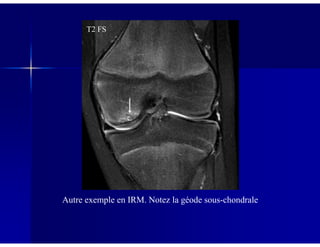

Autre exemple en IRM. Notez la géode sous-chondrale